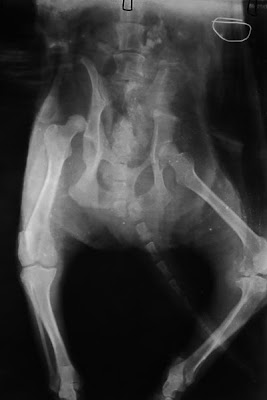

Durante o exame clínico foi-lhe diagnosticada uma luxação coxo-femoral traumática (desarticulação da cabeça do fémur com a bacia). O animal também estava desidratado e subnutrido.

Sob anestesia foi possível recolocar o fémur na posição normal tendo sido aplicada uma ligadura específica (ligadura de Ehmer) de modo a proteger a articulação nos primeiros dias. O restante tratamento consistiu em repouso, medicação anti-inflamatória e protector articular.